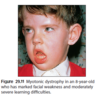

What are the signs/symptoms of dystrophia myotonica?

Newborns: hypotonia, feeding and respiratory difficulties, thin ribs, talipes at birth, oligohydramnios, reduced fetal movemnets at pregnancy.

Later:

- myopathic facial features (‘haggard’ appearance)

- dysphagia

- learning difficulties

- myotonia (prolonges muscle tensing) e.g. slow release of handshake, difficulty releasing tightly clasped fist

- initially distal weakness of arms and legs

- dysarthria

- males - baldness, testicular atrophy

- cataracts, bilateral ptosis

- T2DM

- cardiac dysrrhythmias